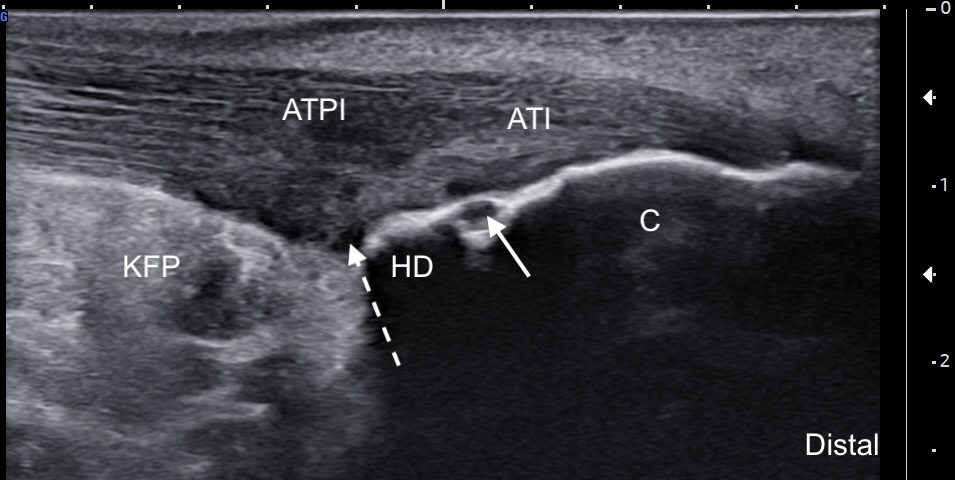

Labeled short-axis ultrasound image of the insertional Achilles tendon, at the level of the superior edge of the calcaneus showing increased thickness, hypoechogenicity, and partial tearing of the deep tendon fibers.

Labels: AT: Achilles tendon, C: calcaneus, solid arrow: retrocalcaneal bursa, dashed arrow: partial tear.

Image Interpretation: Chronic insertional and pre-insertional Achilles tendinosis associated with a Haglund's deformity. There is subcortical cystic change at the level of the Haglund deformity, consistent with chronic Achilles tendon pathology. Partial tearing of the deep fibers of the Achilles tendon is noted adjacent to the bony prominence. A mild retrocalcaneal bursal effusion is also present.